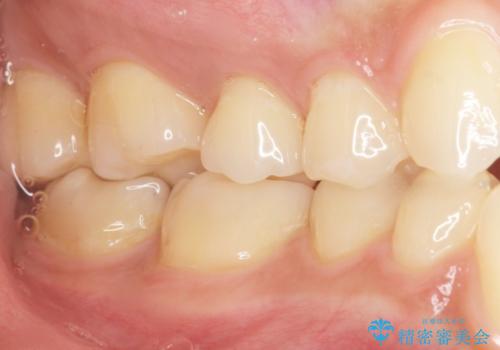

不適合なレジンを除去し、セラミックインレーによる治療を行いました。(右上76左上67右下7の計5本)

気にされていたフロスをした時のにおいがなくなり、喜んで頂けました。

治療終了後半年のメンテナンス時には「咬み合わせもばっちりです!」とおっしゃって下さいました。

インレーの種類:セラミックインレー e-max press